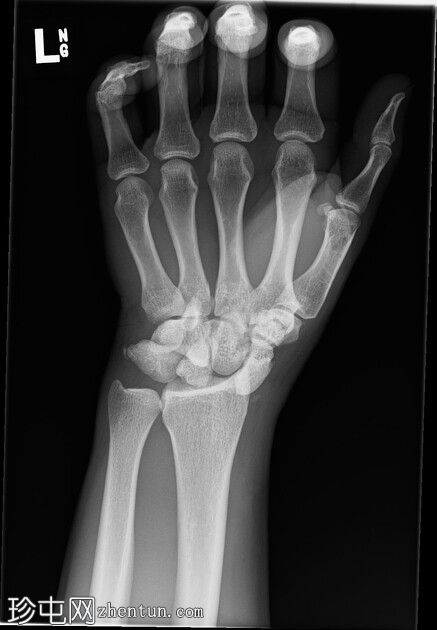

左腕

X光片

正面

斜位

侧面

前后位:舟月骨间隙明显增宽,月骨呈三角形。侧面显示月骨掌侧脱位,头状骨和桡骨远端保持正常排列,符合月骨脱位。陈旧性背侧三角骨骨折。腕部软组织肿胀。